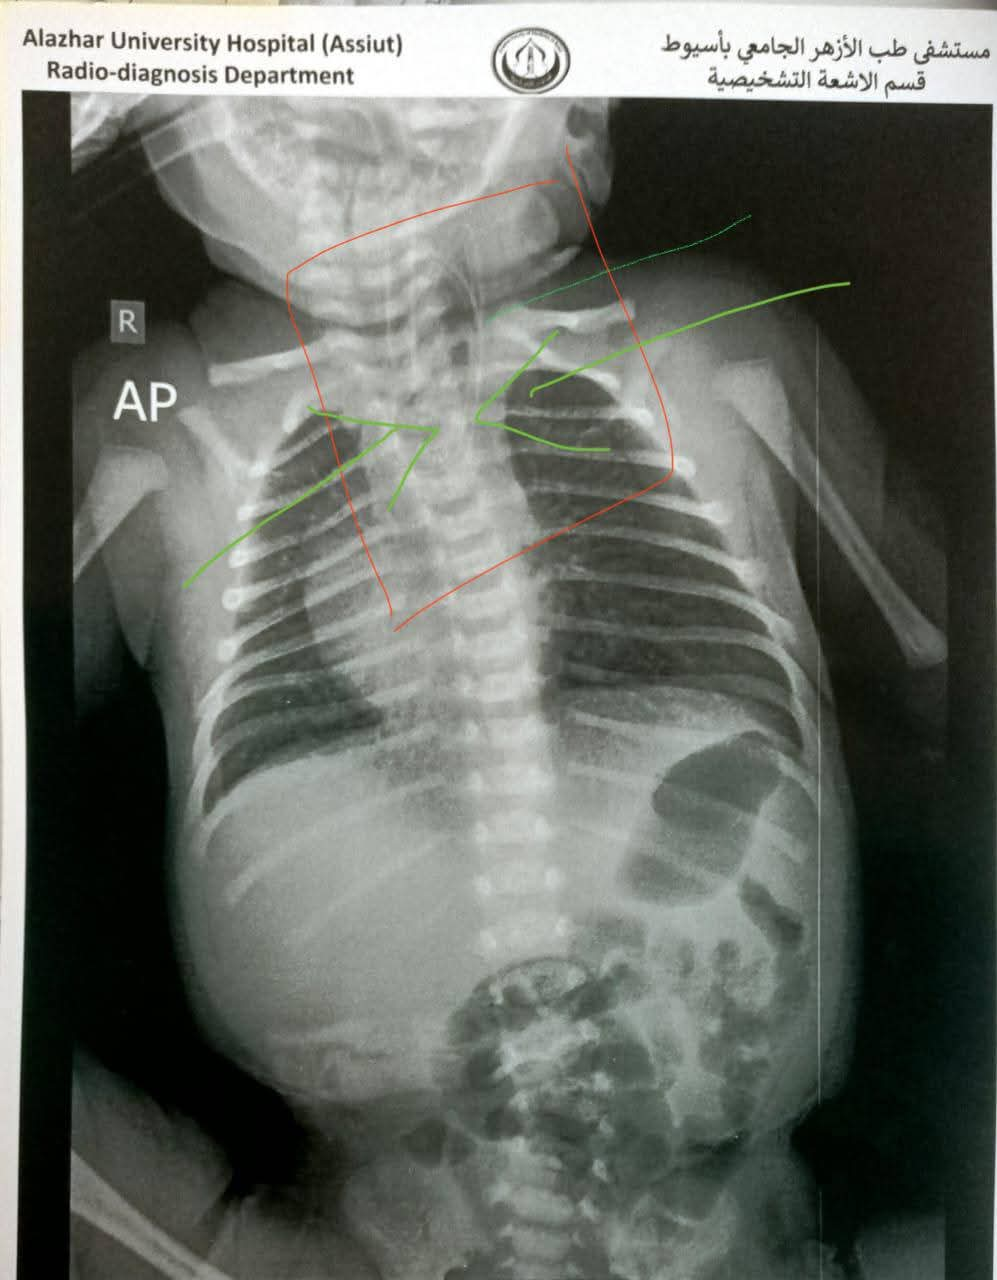

وصرح الدكتور إبراهيم شعلان، عميد كلية طب أسيوط رئيس مجلس إدارة المستشفى الجامعي، أن المستشفى استجاب على الفور لشكوى محولة من منظومة الشكاوى بمجلس الوزراء متضمنة حالة الطفل الرضيع، والمحول من إحدى مستشفيات قنا، حيث استقبل قسم الحضانات الطفل، وتم اتخاذ جميع التدابير والتجهيزات اللازمة من فحوصات طبية وأشعة وتحاليل قبل إجراء العملية.

وأضاف عميد كلية الطب أن الأشعة والفحوصات أكدت بوضوح الانسداد الكامل بالمريء مع وجود ناسور بحجم كبير، وهو ما عجل بدخول الطفل غرفة العمليات لإجراء واحدة من أعقد جراحات الأطفال، وتتطلب دقة ومهارة عالية من الفريق الجراحي.